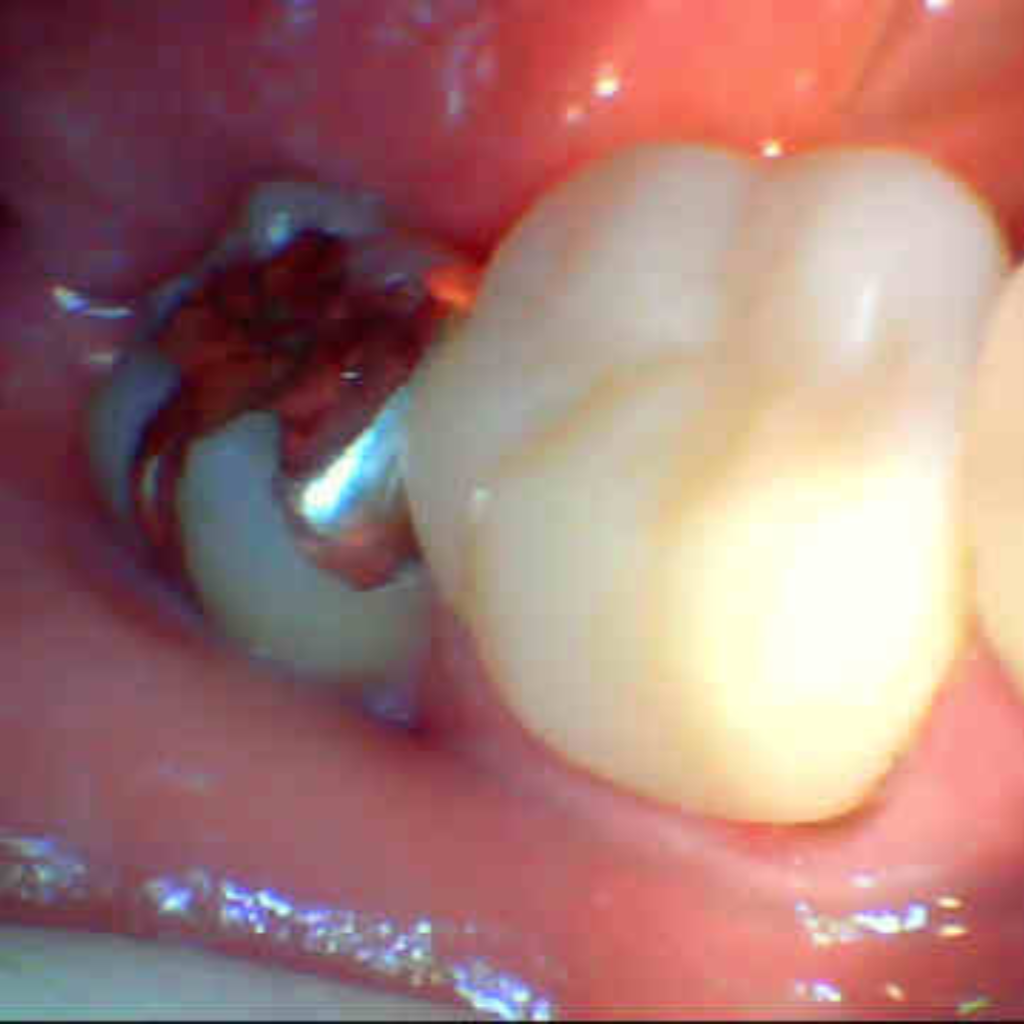

CAD/CAM冠の保険適用の治療例

治療前

左下6

治療後